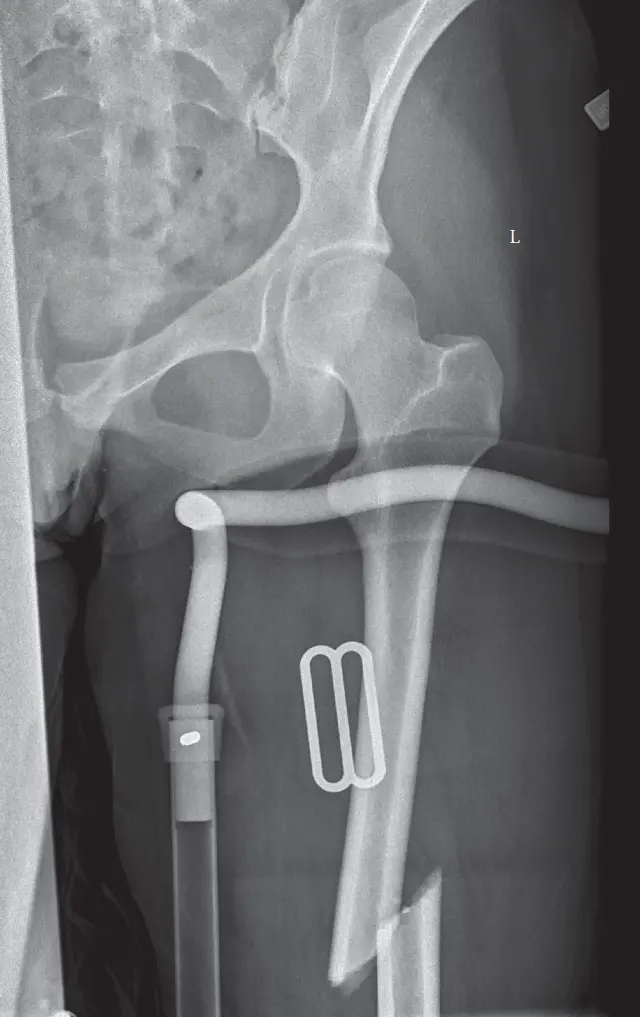

كسور عظم الفخذ لدى الشباب هي إصابات خطيرة تتطلب غالبًا علاجًا جراحيًا دقيقًا لاستعادة وظيفة الطرف. يشمل العلاج التثبيت الداخلي بالمسامير أو الشرائح، يليه برنامج تأهيل مكثف لضمان التعافي الكامل والعودة إلى الأنشطة اليومية.

2. الفحوصات التصويرية

الأشعة السينية (Plain Radiographs):

- هي الخطوة الأولى والأكثر أهمية. يتم أخذ صور بالأشعة السينية من الأمام والخلف (AP) ومن الجانب (Lateral) للفخذ بالكامل، بما في ذلك مفصل الورك والركبة.

- تساعد هذه الصور في تحديد موقع الكسر، نوعه (بسيط، مفتت، حلزوني)، درجة الإزاحة، ووجود أي كسور أخرى في نفس العظم أو العظام المجاورة.